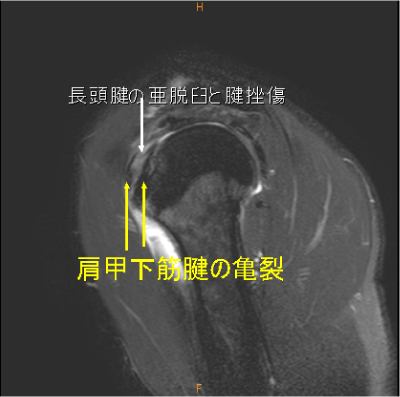

MRI所見

Hidden lesion症例(長頭腱亜脱臼、肩甲下筋腱損傷)

Hidden lesion(長頭腱亜脱臼+肩甲下筋腱断裂), 長頭腱亀裂